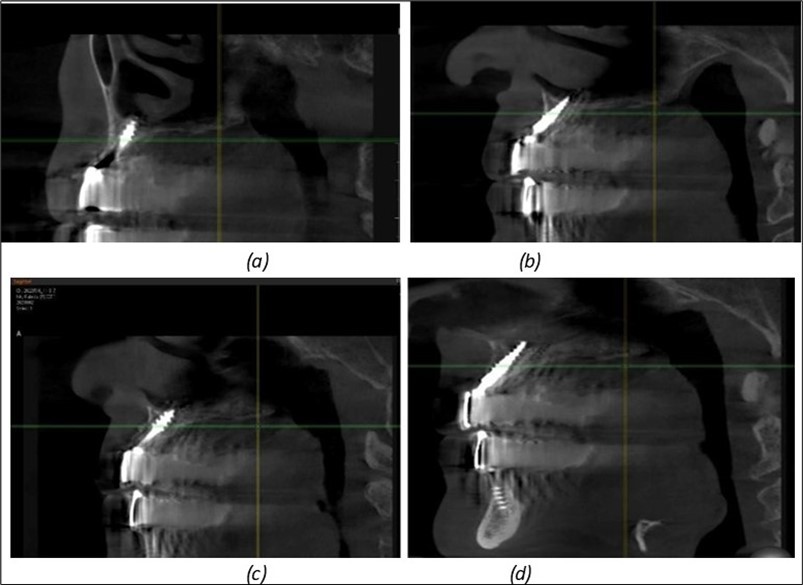

Figure 10.Implants in the palatal sinus cortical area to avoid bone grafting: (a) BCS implant partially fixed in the graft material mass, partially in the palatal cortex; (b) Implant fixed in the palatal cortex at the junction with the nasal cortex, behind the graft material mass.

Figure 11.Implants in the anterior area anchored in the nasal cortex (BCS and TPG): (a), (c) – BCS implants fixed in the nasal cortex; (b), (d) – TPG implants fixed in the second nasal cortex with compression in the trabecular area.